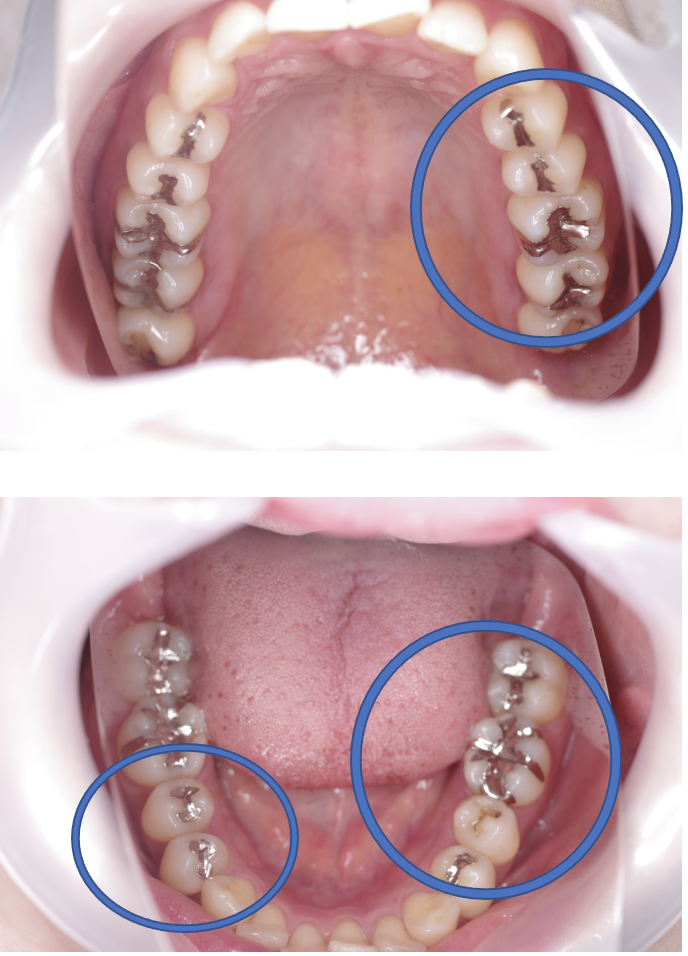

Before

| 備考 | 院長より 銀歯の内部に虫歯が進行してしまっていたケースです。中を開けて見てみると、外から想像するよりもはるかに虫歯が広がってしまっていました。幸運にも神経を保存できたので、生きた臓器としてまだ使うことが可能です。今回は部分的な詰め物で対応することができたケースです。 |